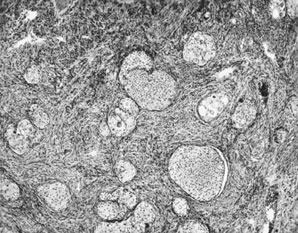

The ovarian tumors associated with mucinous tumors that are disseminated throughout the peritoneum are of two types. Tumors composed of pools of mucin with scanty simple or focally proliferative mucinous epithelium displaying minimal cytologic atypia and rare mitotic figures have been designated DPAM along with the abdominal disease (Fig. 9). Additional morphologic features that are characteristically seen in these secondary ovarian lesions include strips of mucinous epithelium floating in mucin pools, often with a hypersecretory or hypermucinous appearance. These are nearly always associated with appendiceal adenomas lacking significant atypia. The ovarian mucinous proliferation closely resembles the peritoneal mucinous lesions as well as the appendiceal adenoma.

Fig. 9. Disseminated peritoneal adenomucinosis. In this form of pseudomyxoma peritonei, large pools of acellular mucin dissect through tissues. Occasional mucinous glands, seen at upper left, display minimal cytologic atypia.